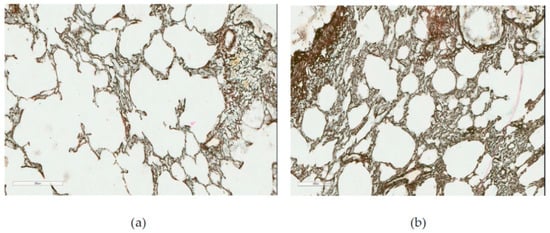

At the same time, a histological investigation of the lung tissue by optical microscopy did not reveal, even towards the end of the experiment, any cellular fibrotic nodules typical of experimental pneumoconioses, or any thickening of interalveolar septae together with their diffuse fibrosis. On the contrary, the septae became thinner or were even destroyed (emphysema), while the reticulin framework was no coarser than in the control rats (Figure 6).

Figure 6. Rat lungs (a) after 10-month inhalation exposure to NiO-NPs and (b) in the control group of the same exposure period. Gomori’s silver impregnation, magnification: 400×. See description in the text.